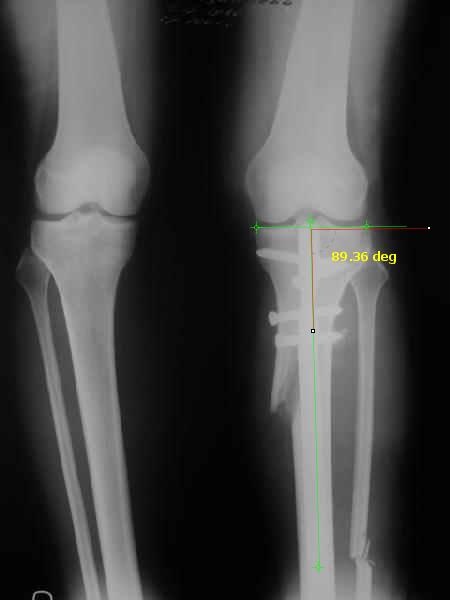

Снимки в приложении - фас сравнительный с неоперированной ногой. Жду критики.

It is very interesting to me that as you have derotated the tibia you have centred the patella, I think and the prox tibia looks much more anatomic.

The analysis in the attached images is direct, just using the tools.

Tibial tilt is perhaps more than you want but the tibial correction is to 90 (very slight over

correction.

Will need full length views to tell us about the hka but it appears neutral.

Measurements took 4 mins